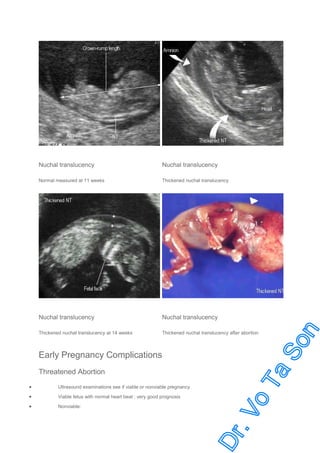

Nuchal Translucency (NT)

NT : small fluid collection beneath skin at back of the fetal neck

Measured at CRL 35-80 mm (10-14 week)

Measured on midsagittal scan (plane for CRL)

The best sonomarker for screening Down syndrome

Abnormal if > 95th percentile (> 2.5-3.0 mm)

Thickened NT increased of aneuploidy, anomaly especially cardiac defect

Nuchal translucency

Normal measured at 11 weeks

Thickened nuchal translucency

Thickened nuchal translucency at 14 weeks

Thickened nuchal translucency after abortion

Early Pregnancy Complications

Threatened Abortion

Ultrasound examinations see if viable or nonviable pregnancy

Viable fetus with normal heart beat : very good prognosis

Nonviable: